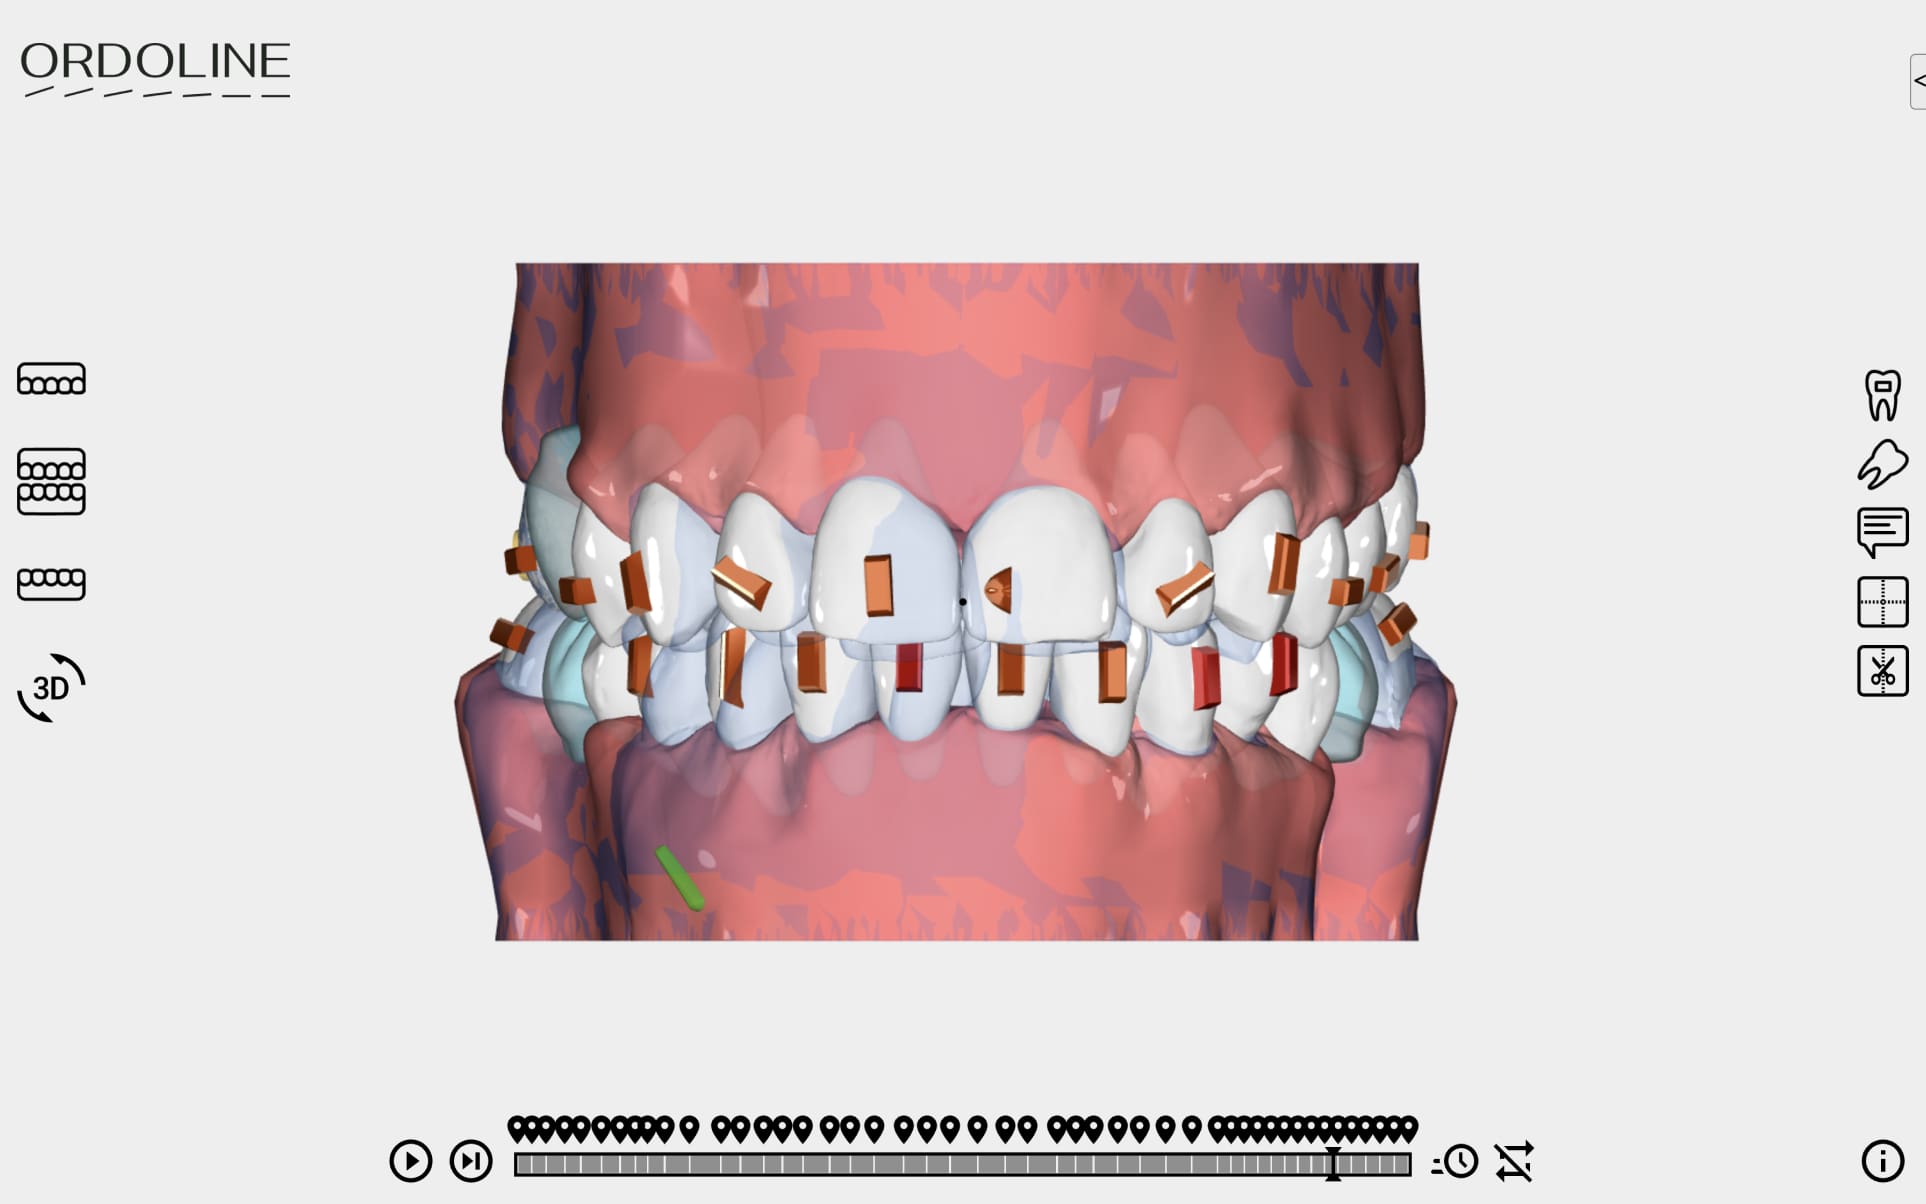

3D Plan

Treatment results